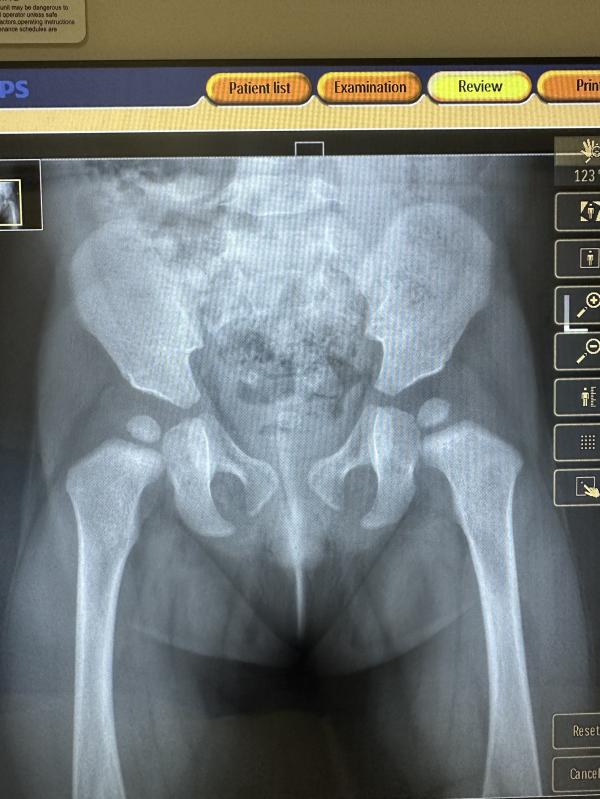

А теперь ставят косвенные признаки дисплазии в год

Гайсин, а что там? угол неправильный? или размер ядер не устраивает человека, кто делал рентген?

Если бы хоть что то кто то нормально объяснил, а то как всегда, у вас косвенные признаки дисплазии. Нужен ортопед вот направление, до свидания.

@irishka.v.i.p, если была бы дисплазия в виде вывиха и подвывиха на рентгене сразу было бы видно, что сустав не в вертлужной впадине. Сходите к Гайсину, Джубаева, Лиссогор тоже вроде неплохой

У вас не критично все можно исправить у нас почти ядра не было мы в 4 месяца обнаружили вылечили слава богу 🙏 ну все как всегда массаж парафин электрофорез,д3 кальций пить усиленно